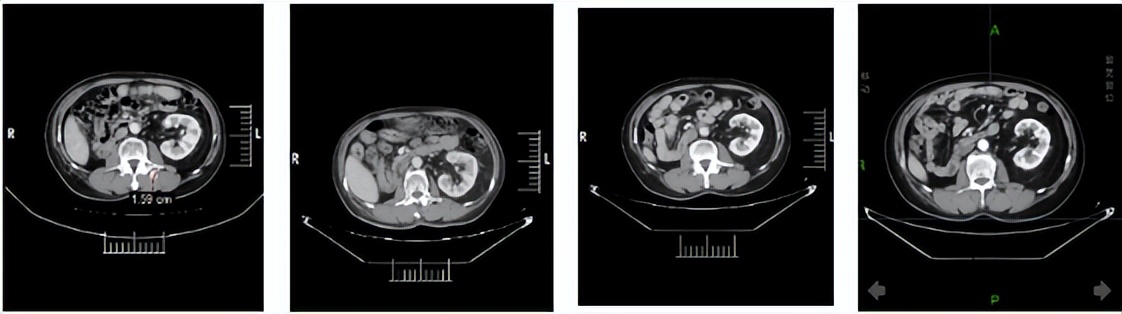

2024年1月3日:治疗4个月后,首次达到PR。

2024年5月9日,决定永久停用信迪利单抗,下调一个剂量水平(4mg,po,qd,D1-14,q3w)恢复呋喹替尼治疗。自此,截至2026年3月30日,呋喹替尼单药治疗约2年且仍在维持中。2026年3月12日行最近一次疗效评估仍处于PR,PFS已达30.4个月。

靶病灶T01:左肾下极

靶病灶T02:左肾上极

靶病灶T03:左侧肾上腺

靶病灶T04:左侧竖脊肌